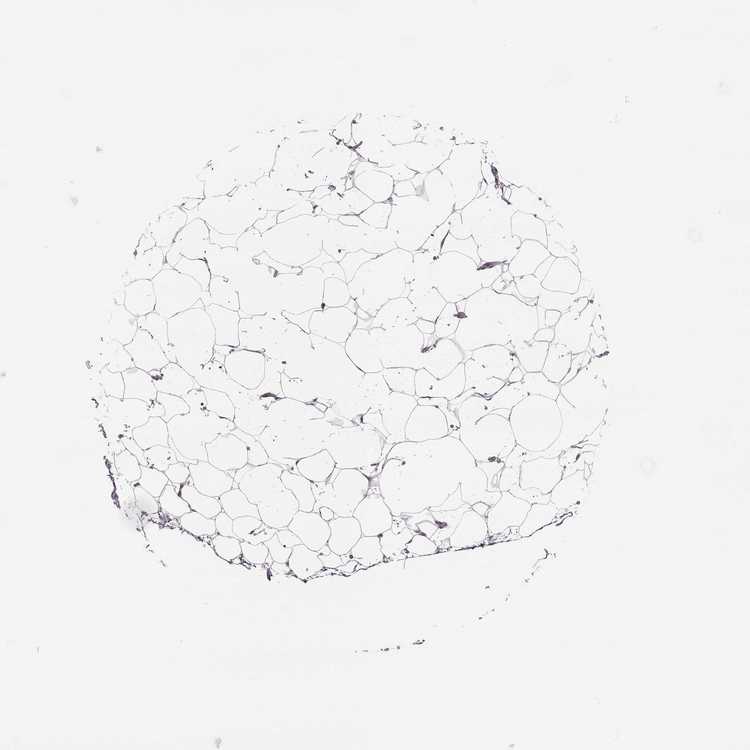

SOFT TISSUE 1 - Antibody stainingi

Antibody staining in the annotated cell types in the current human tissue is reported as not detected, low, medium, or high, based on conventional immunohistochemistry profiling in selected tissues. This score is based on the combination of the staining intensity and fraction of stained cells.

Each image is clickable and will lead to virtual microscopy that enables deeper exploration of all samples and also displays staining intensity scores, fraction scores and subcellular localization as well as patient and tissue information for each sample.

Antibody HPA005753Antibody HPA050656

Fibroblasts Not detectedNot detected

SOFT TISSUE 2 - Antibody stainingi

Peripheral nerve Not detectedNot detected